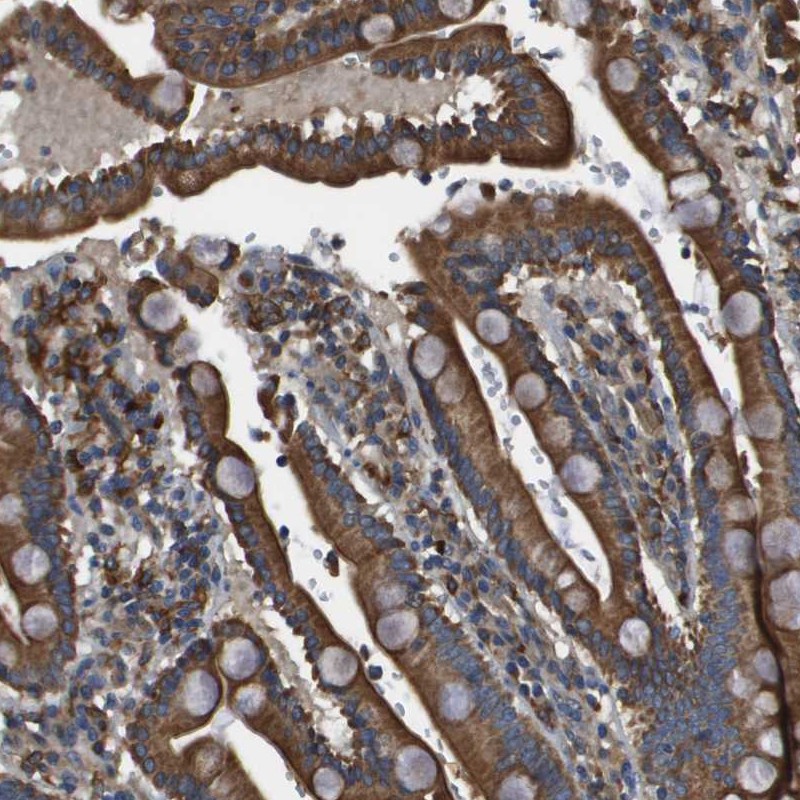

Immunohistochemical staining of human duodenum shows strong cytoplasmic positivity in glandular cells.